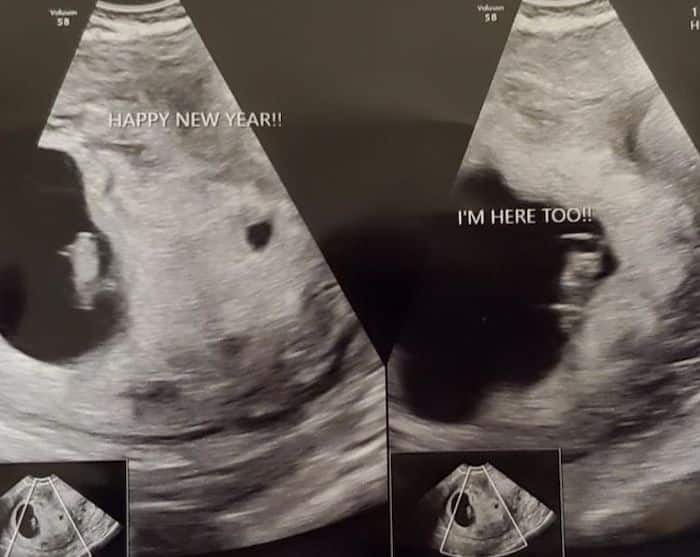

Early Twin Ultrasound at 7 Weeks

Yes! You’d need to have an ultrasound at 7 weeks to confirm a twin pregnancy. Your twin belly at 7 weeks may not look like much of a belly at all, so getting in to your doctor for an ultrasound is key to find out if you’re really having twins.